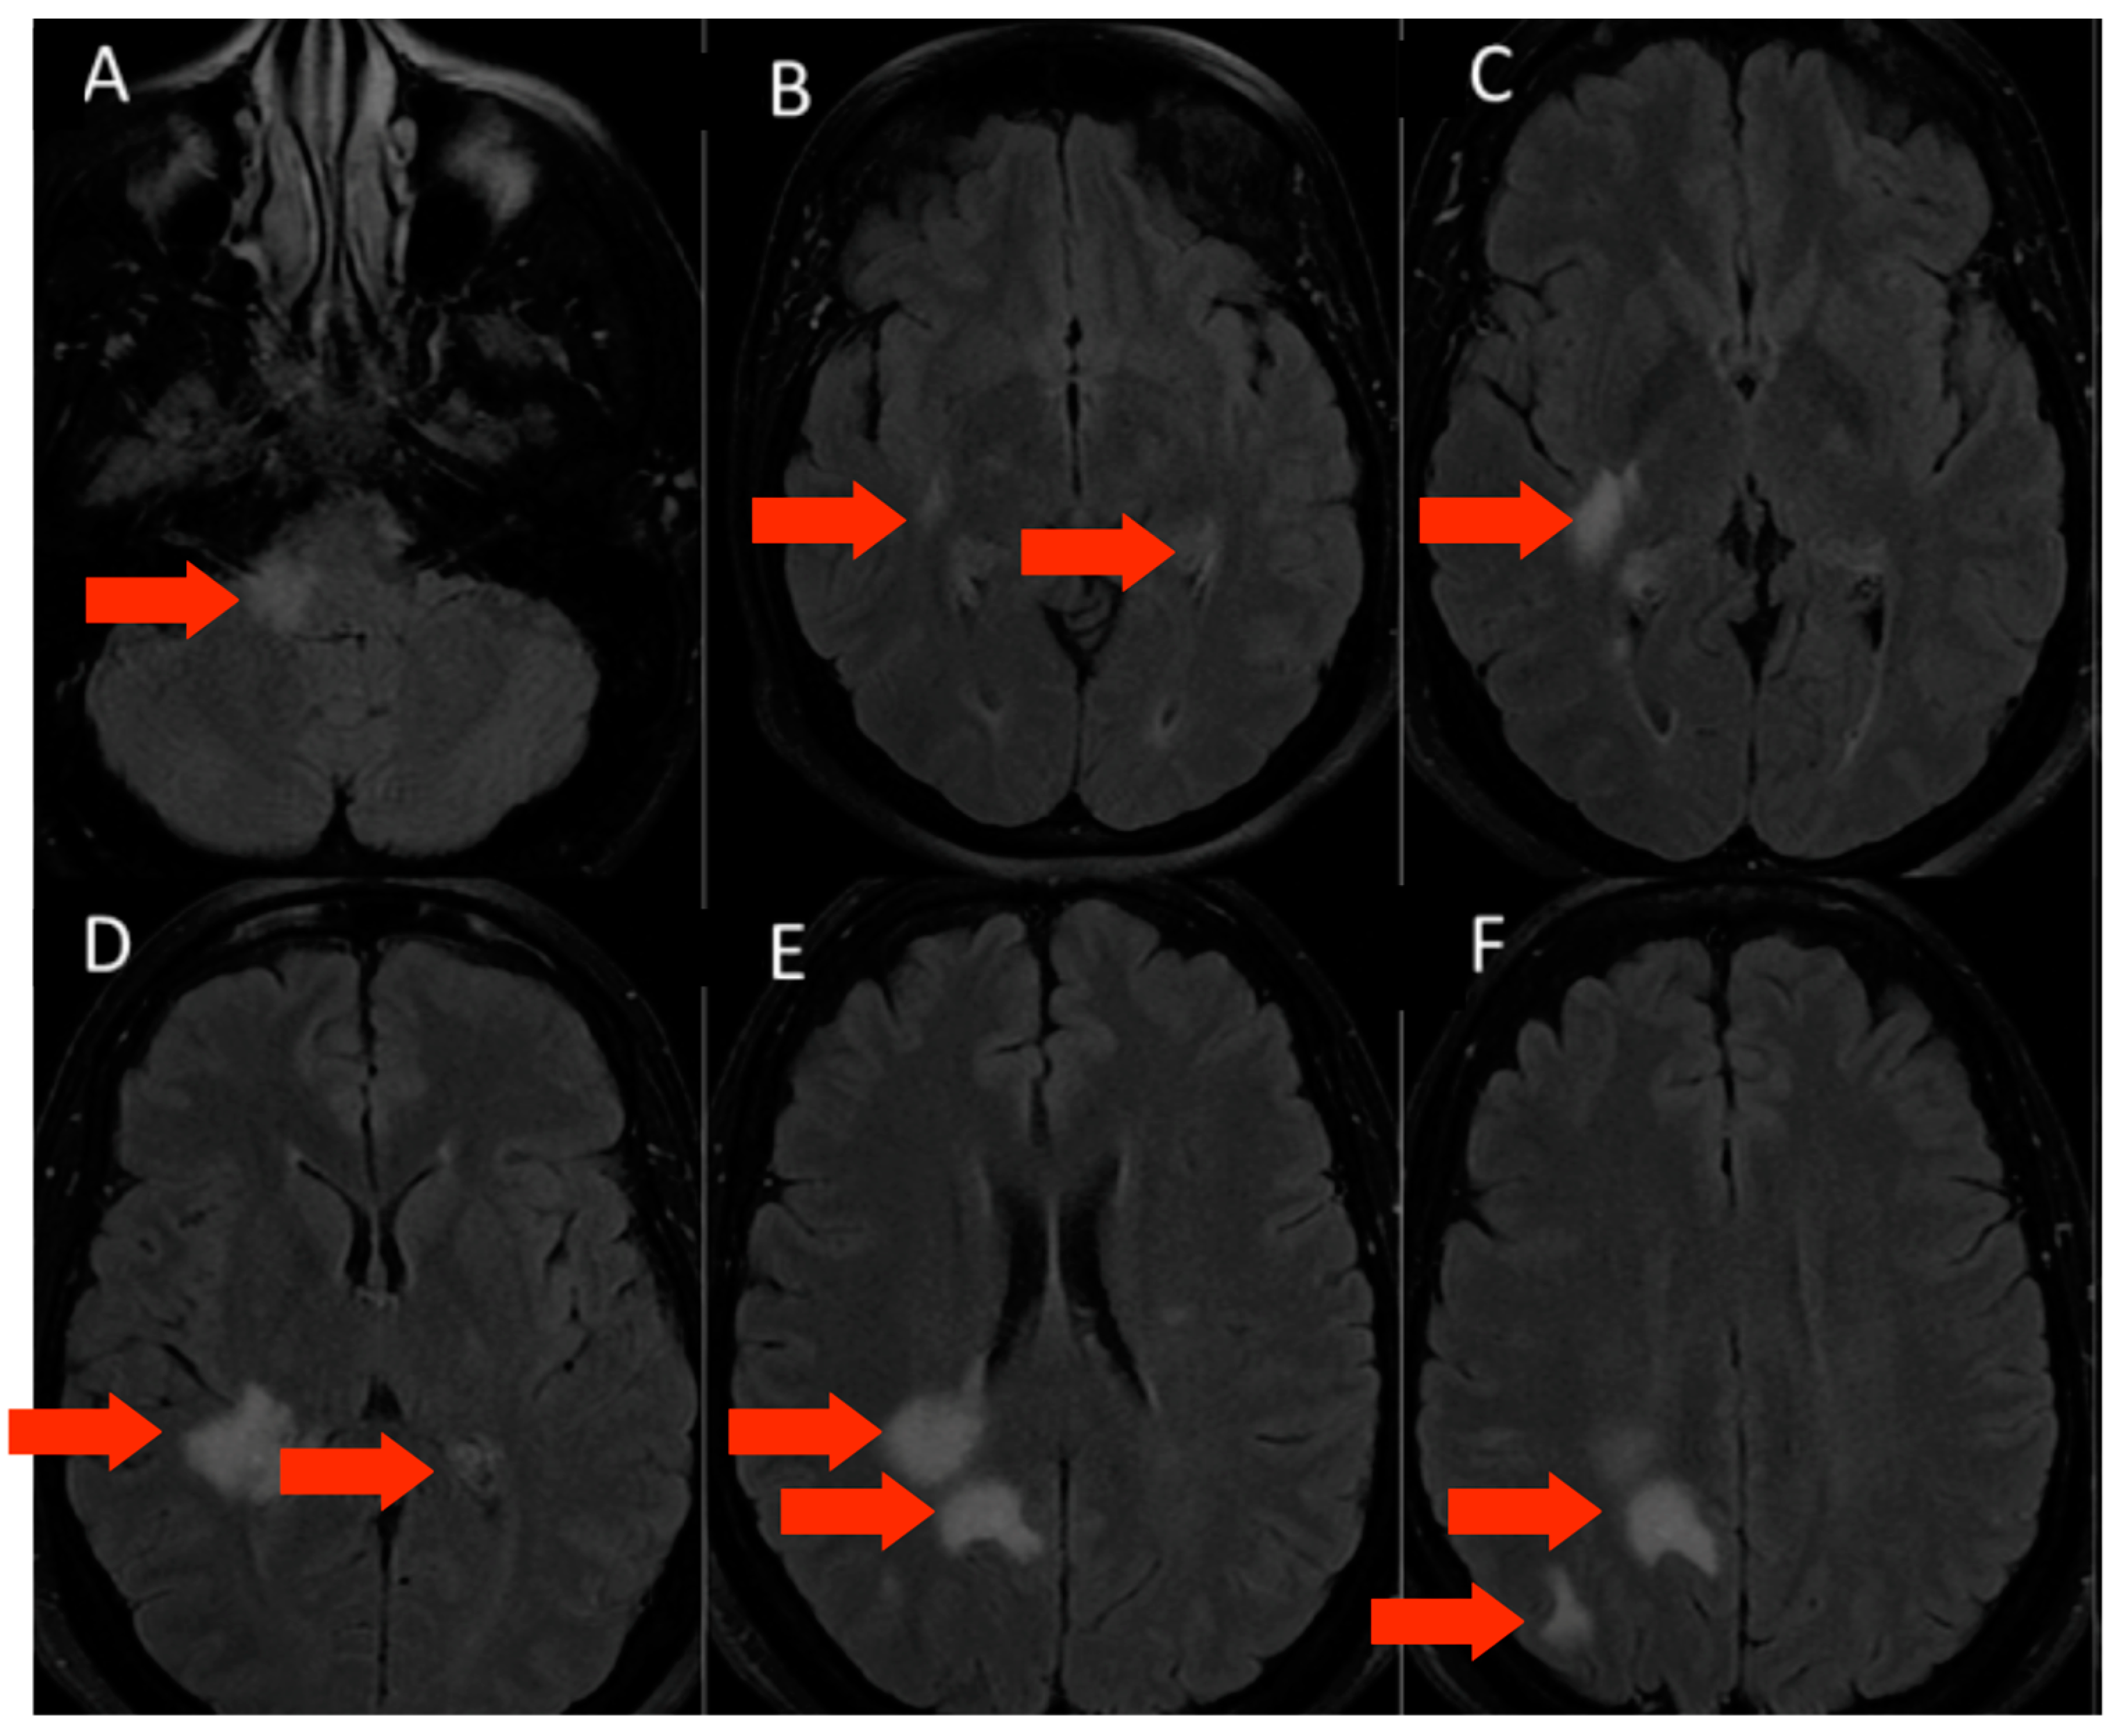

3.1.3. Patient 3